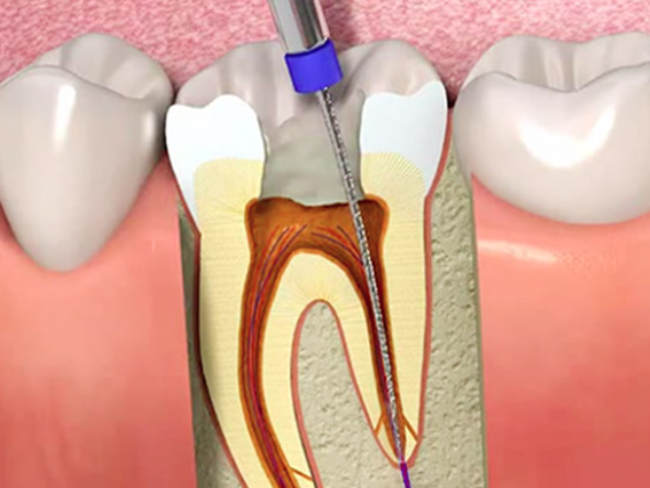

ENDODONCIA